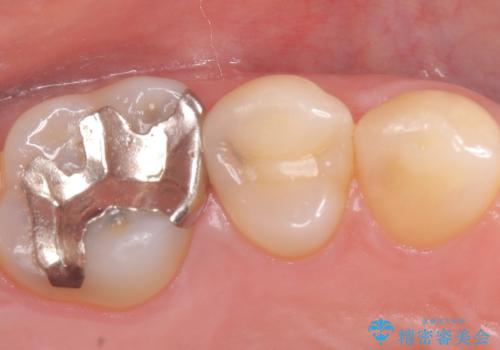

セラミックインレー 虫歯の治療

- 定期健診で虫歯が見つかり、治療が必要となりました。材料の物性を説明し、セラミックインレーでの治療となりました。

接着操作時にはラバーダム防湿を行いました。